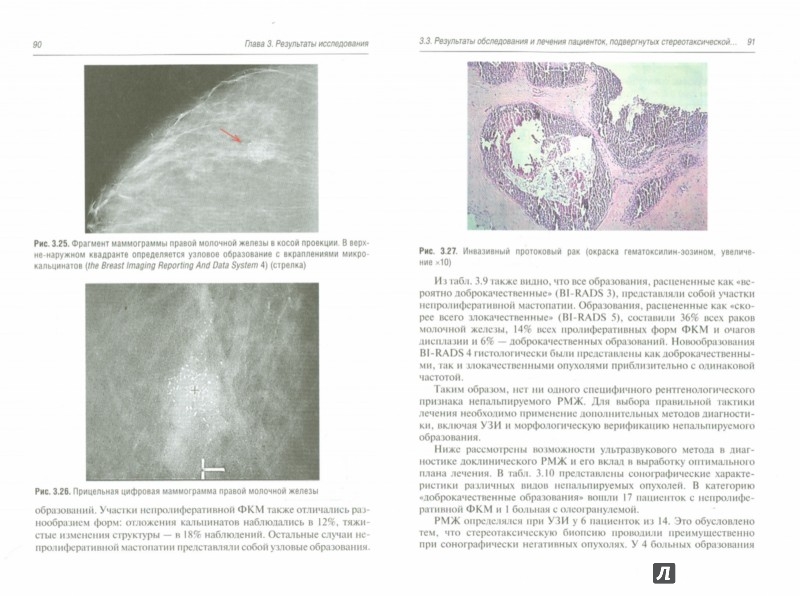

Исследование: микропрепарат молочной железы в медицине

Раздел: Снимки-откровения